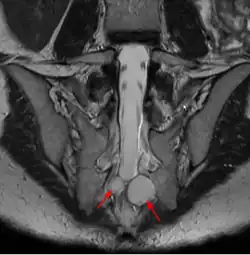

| MRI image showing a Tarlov cyst | |

MRI

MRI, or Magnetic Resonance Imaging, is considered the imaging study of choice in identifying Tarlov cysts. MRI provides better resolution of tissue density, absence of bone interference, multiplanar capabilities, and is noninvasive. Plain films may show bony erosion of the spinal canal or of the sacral foramina. On MRI pictures, the signal is the same as the CSF one.